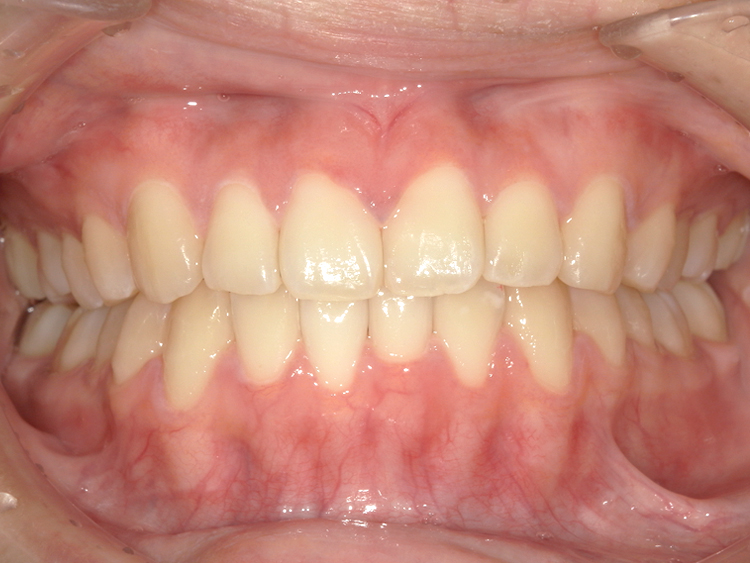

症例4

Before

After

| 主訴 | 上下前歯のがたつき |

|---|---|

| 年齢 | --- |

| 治療 期間 |

約9ヶ月 |

| 治療 内容 |

インビザラインiGoで上下顎の治療。 |

| 治療費 | ¥550,000(税込)/調整料含む |

| 治療のリスク | 矯正終了後は、リテーナーを指示通りに使用し、歯の後戻りを防ぐ必要があります。 |